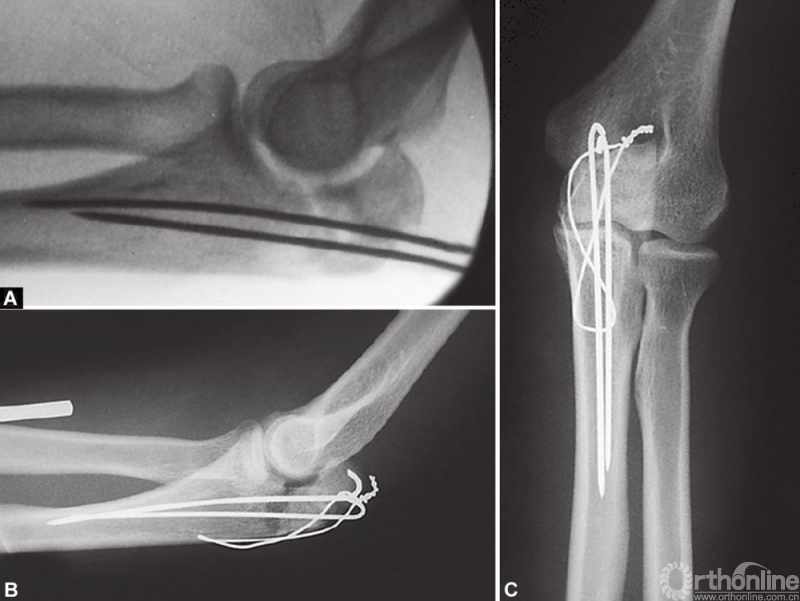

标准的Weber-Vasey固定,常见问题是短克氏针放置在髓腔内而不是穿透尺骨前侧皮质,肘关节运动容易使其退出,损害皮肤,穿透皮肤,有时甚至发生脱落。

Weber -Vasey技术改良方法很多,有两个特别有用。一是使用长克氏针,到达尺骨髓腔的远端。尺骨髓腔的自然弯曲为直克氏针提供了可靠的三点固定,产生摩擦力,防止克氏针退出。二是克氏针贯通冠状突稍远端尺骨前侧皮质(图1A~C),使用该方法时,克氏针不得超过前侧骨皮质2~3mm,否则可能损害前侧的神经血管。两个方法中,近端克氏针和钢丝都必须很好地弯曲并包埋在鹰嘴尖端,以防止造成损害。

“8”字钢丝环应该放置在三头肌腱下面,而不是绕在克氏针的近端周围。使用宽口径导针可以使钢丝顺利穿过。在远端,钢丝环穿过2mm钻头在骨折线远端2~3cm钻的一个孔。钢丝环在鹰嘴尖端的近端拧紧,尾部剪断,弯曲并埋入肱三头肌腱下。钢丝应避免在尺骨边缘皮下拧紧和打结,否则会造成损害和不适。除了有经验的外科医生,术中常规用X线片检查关节的一致性和植入物的位置。